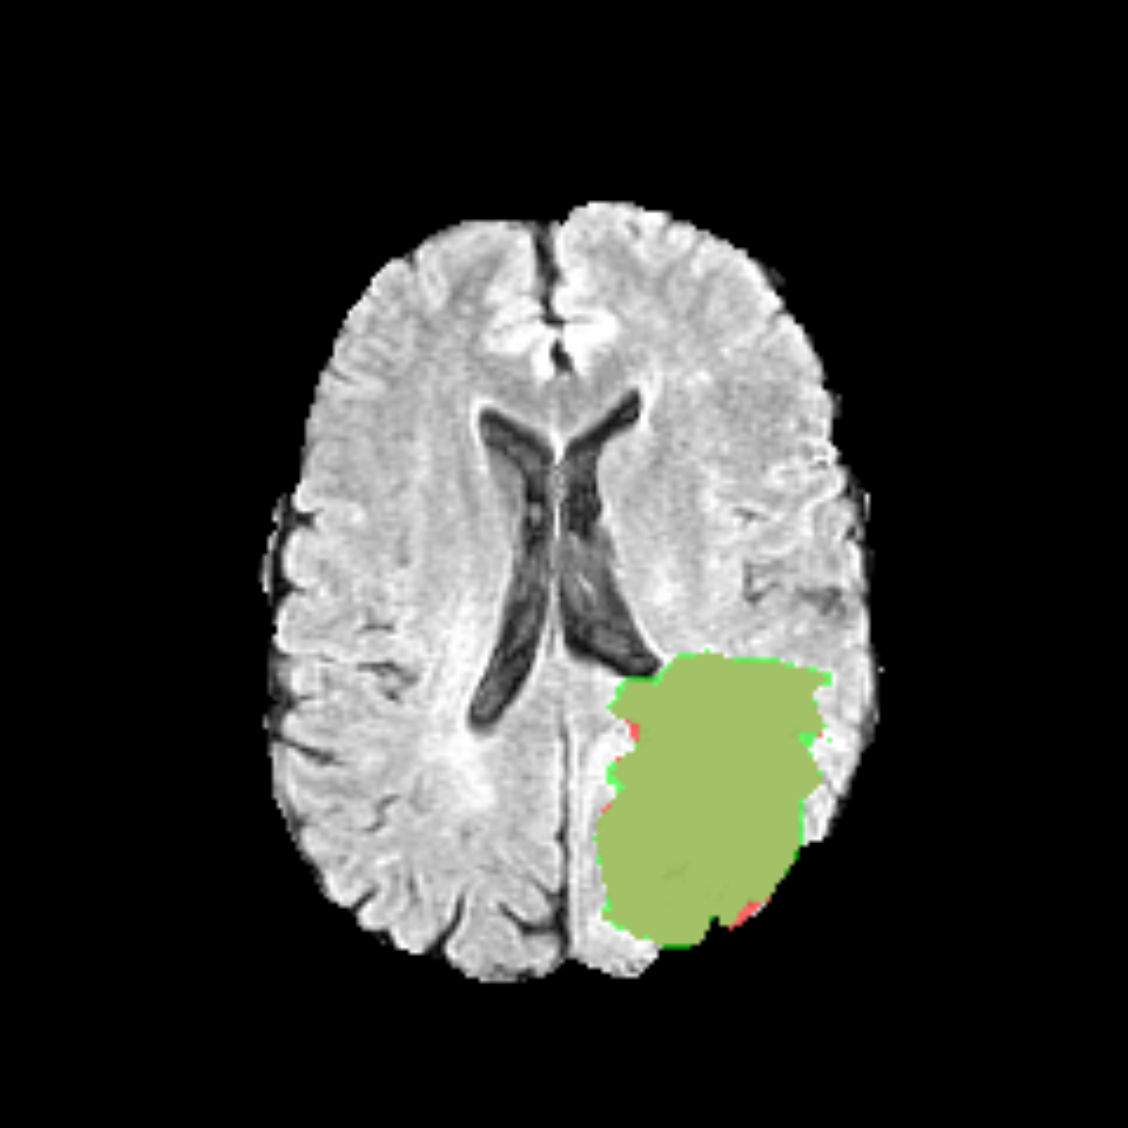

Brain MRI with tumour segmentation overlay

Glioblastoma segmentation overlay on an axial FLAIR slice from the BraTS dataset.